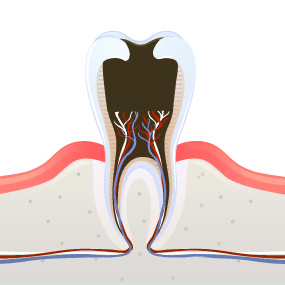

3 신경까지 충치가

진행된 경우신경치료 후 치아를 완전히

덮어씌우는 ‘크라운 치료’ 진행 -